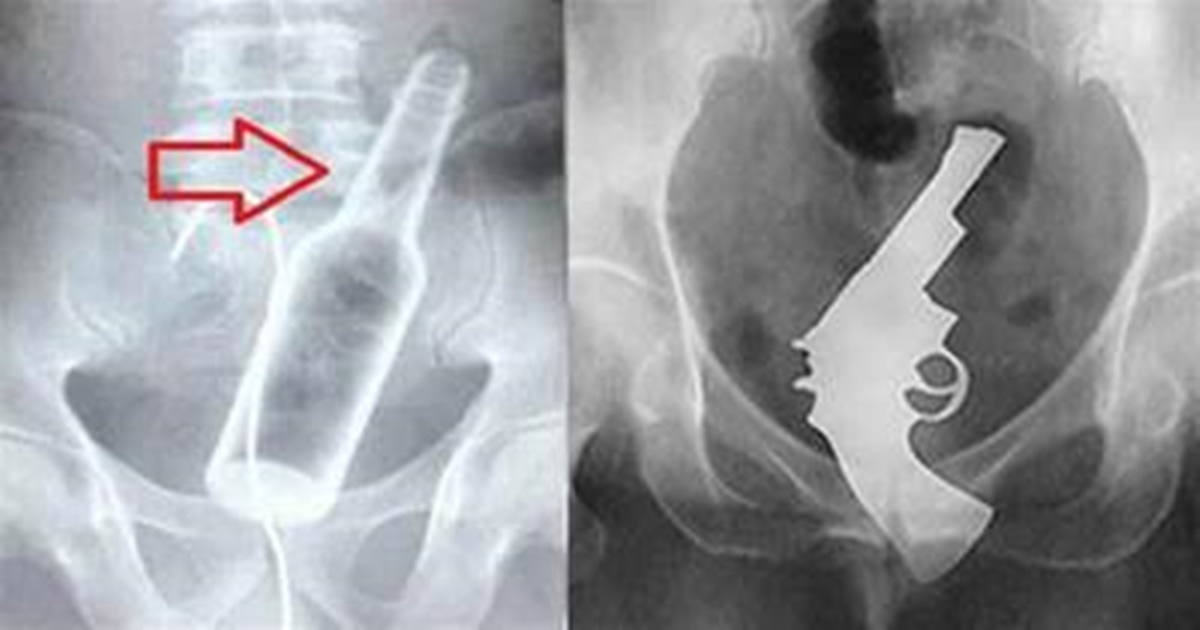

Resolvemos mostrar alguns casos de raios-x onde é possível visualizar vários objetos bizarros no corpo humano, que vão deixa qualquer um chocado com o que vão ver.

Os profissionais de saúde utilizam raios-x para averiguar o local da dor, onde acham coisa bem incomum, em crianças menores é normal eles engolirem objetos sem perceber. Mas entre os maiores de idade, isso pode ser considerado como um distúrbio mental.

O procedimento para a retirada desses objetos pode ser simples, ou até precisar de cirurgia, tudo depende de cada caso de onde está o objeto e seu tamanho conta bastante na hora da avaliação do médico.

Grande parte dos casos não chega ser tão preocupante, mais em alguns casos pode levar o indivíduo a morte, pois os objetos podem perfurar algum órgão fazendo com que a pessoa tenha hemorragia causando óbito do paciente.